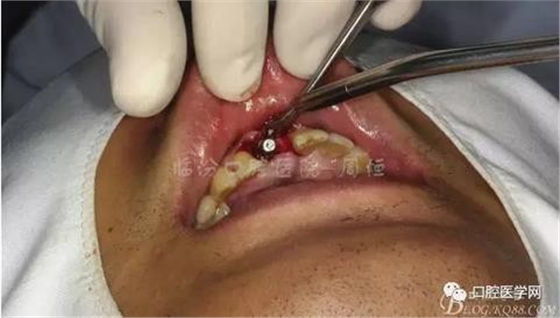

圖5 拔除殘根